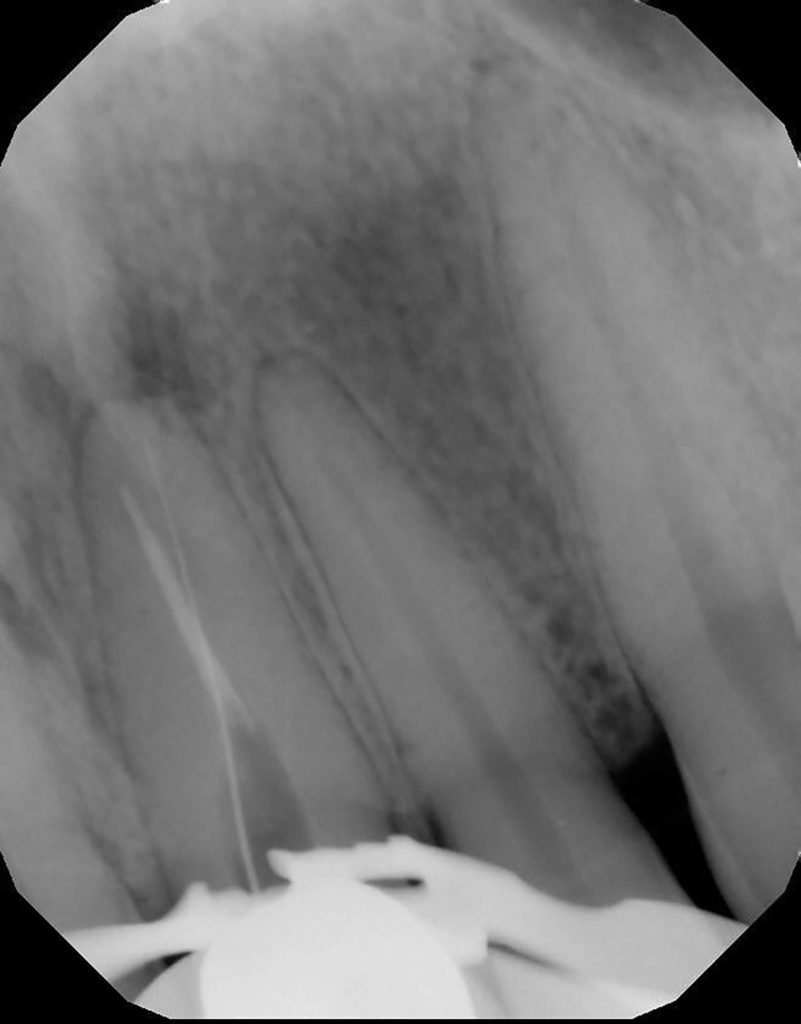

Fun retreatment. Patient had RCT on 9, which was retreated by another endodontist 5 years ago. Patient developed pain and swelling in the area. CBCT revealed a transported canal with a perforation. I was able to locate the canal and hopefully save the tooth!